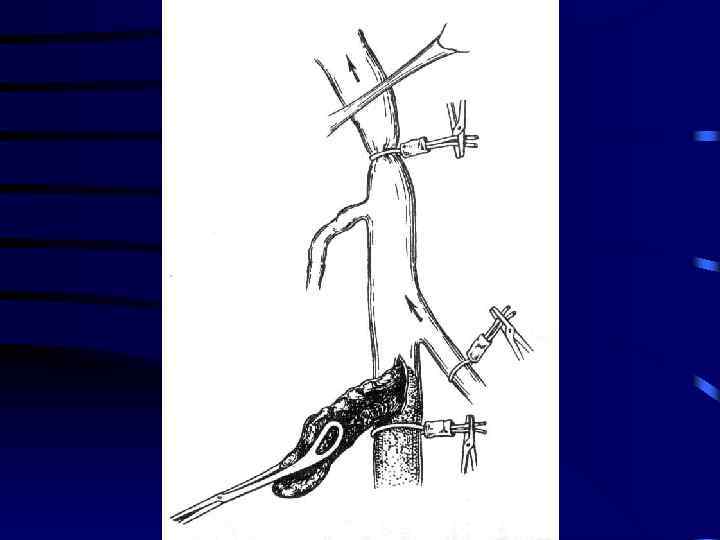

Лечение: 1. Консервативная терапия: a) Эластическое бинтование с возвышенным положением b) Гепарин c) Антибиотики d) Покой 5 -7 суток 2. При флотирующем или эмбологенном тромбозе хирургическое лечение: a) Установка Кава-Фильтра b) Пликация вен выше места тромба